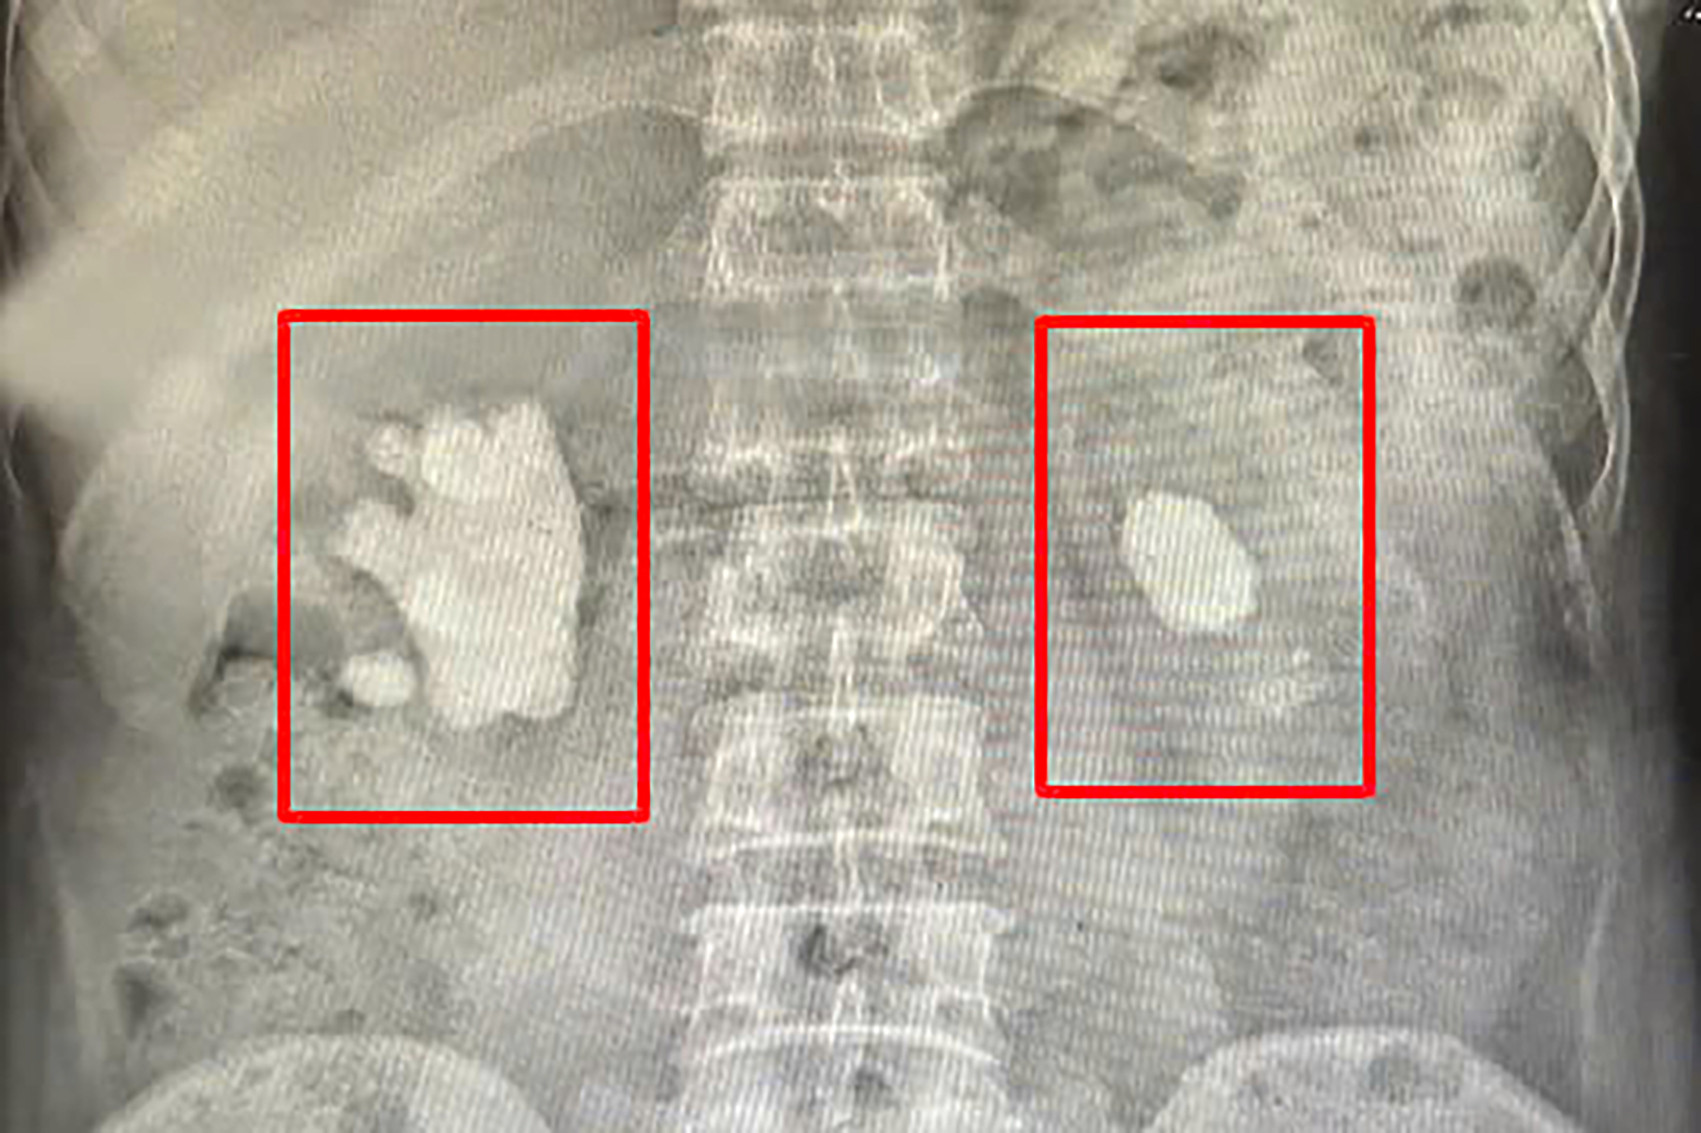

Tại bệnh viện, kết quả chụp x-quang và cắt lớp vi tính cho thấy người bệnh có sỏi thận 2 bên, thận bên phải có khối sỏi lớn hình dạng giống san hô chiếm gần hết bể thận.

Các bác sĩ Khoa Ngoại Thận – Tiết niệu đã hội chẩn và chỉ định phẫu thuật mổ mở lấy sỏi. Quá trình phẫu thuật diễn ra trong hơn 2 giờ, các bác sĩ đã lấy ra 2 viên sỏi, 1 viên sỏi khổng lồ kích thước 3x6cm, nặng gần 100g hình dạng sù sì giống san hô, 1 viên kích thước gần 1cm.